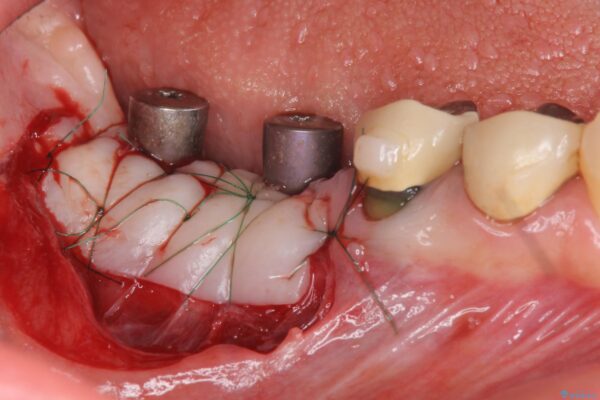

虫歯に伴い歯槽骨の吸収も見られたので造骨後、インプラントを用いて咬合機能を回復します。

治療中

遊離歯肉移植術を伴うインプラント治療 治療中画像 遊離歯肉移植術を伴うインプラント治療 治療中画像 遊離歯肉移植術を伴うインプラント治療 治療中画像 遊離歯肉移植術を伴うインプラント治療 治療中画像 遊離歯肉移植術を伴うインプラント治療 治療中画像 遊離歯肉移植術を伴うインプラント治療 治療中画像